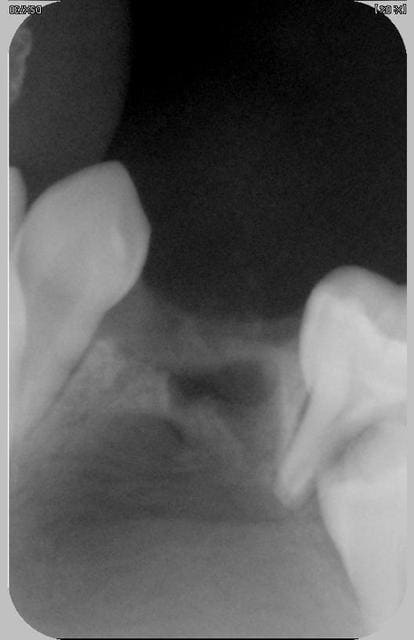

pano comme on a pu

pas de chance,c'est au niveau de 74 qu'on ne voit pas gd chose: une petite rx?

autant pr moi j'ai regardé la 75

la pano n'est vraiment pas terrible,mme le kyste je ne le discerne pas tant(mais où st donc mes lunettes)

par contre tout en bas ,les 2 images,sont les germes de 33 et 34,j'imagine

franchement je ne vois pas gd chose sur ta pano

cependant lapadoué dire que la 74 est saine... euh... pas de carie ,d'accord mais au niveau des racines elles ne me semblent pas d'aspect normal

et puisque kyste il y a on peut s'interroger sur sa vitalité